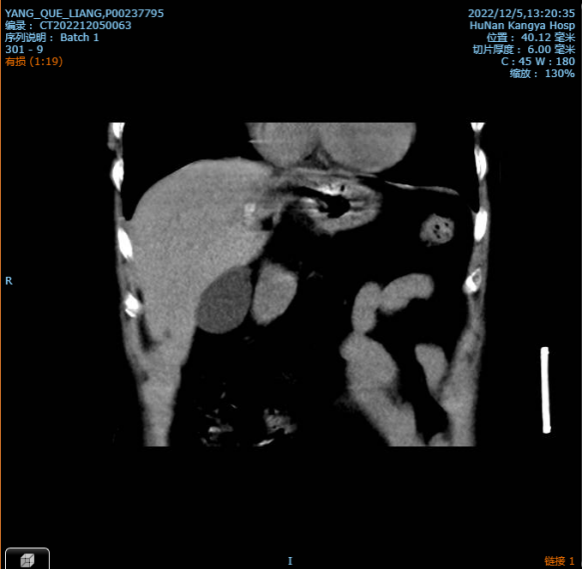

本例手术病人术前检查发现有左肝内胆管多发结石并胆管炎、左肝部分萎缩、胆囊结石胆囊炎、胆源性肝硬化。